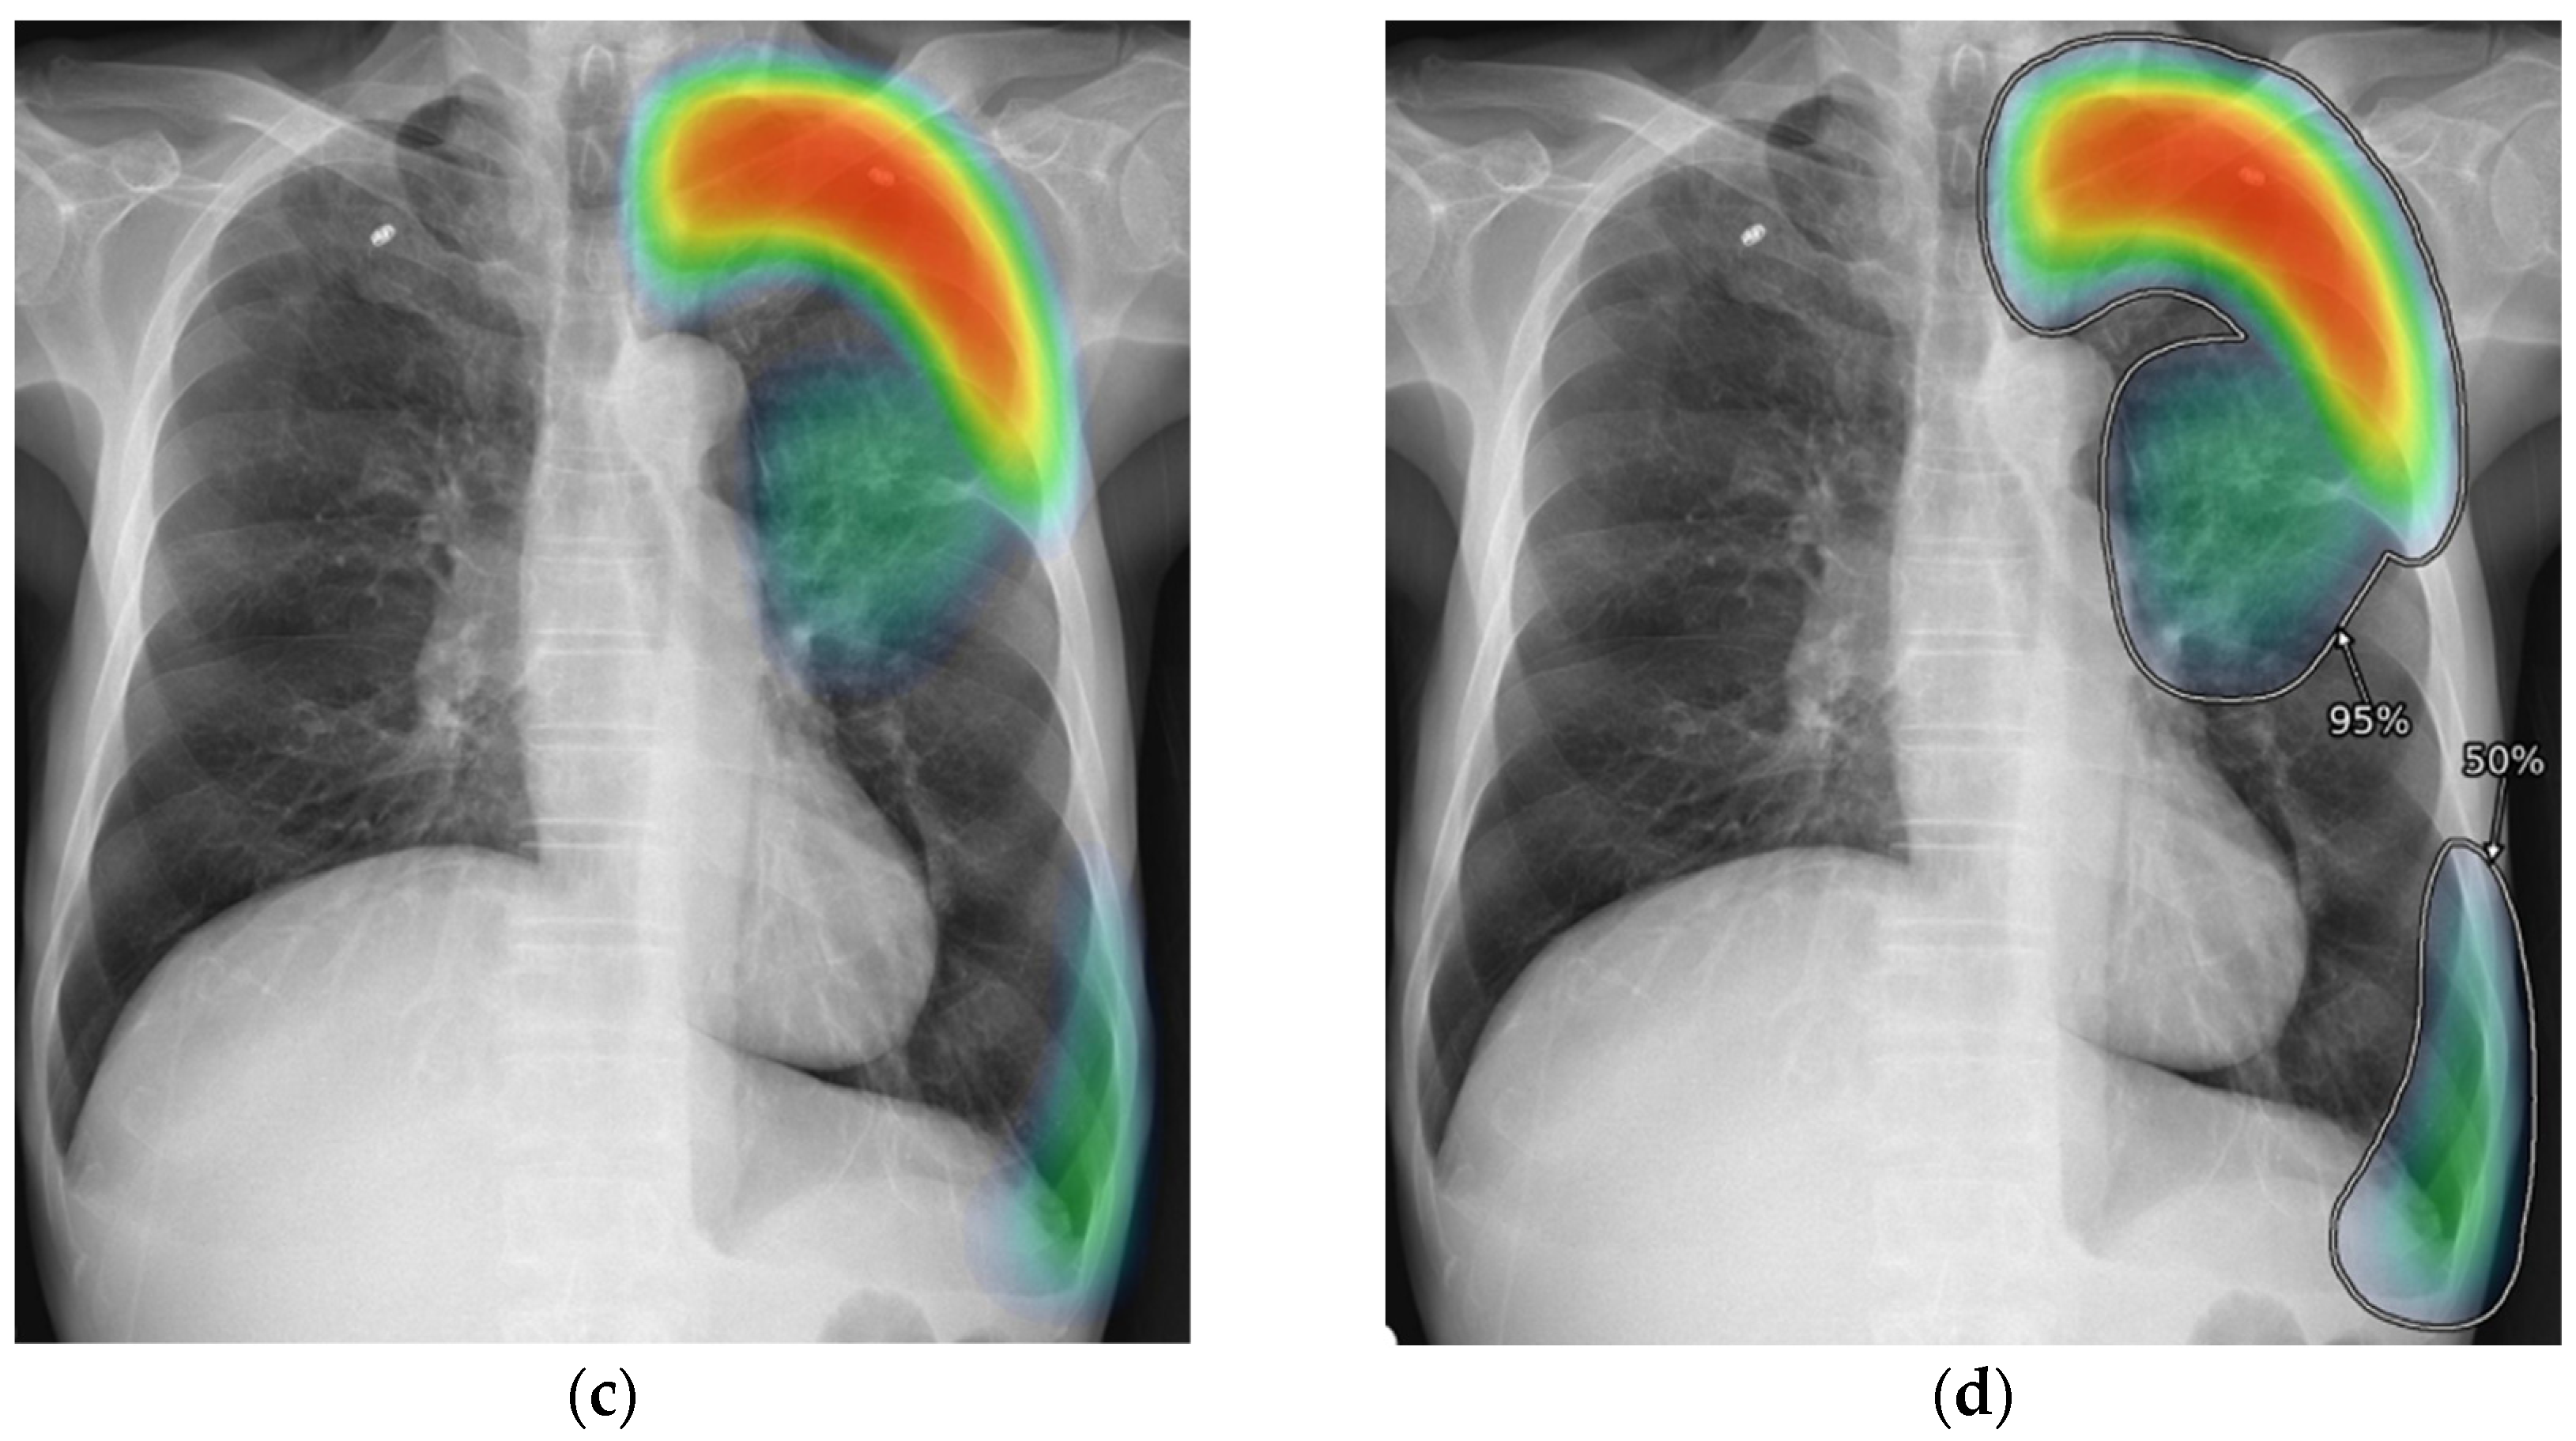

Healthcare organizations use explainable AI to help doctors understand diagnostic recommendations and treatment suggestions. When AI analyzes medical images like X-rays or MRIs, explainable AI shows which specific areas influenced the diagnosis through visual highlights and annotations.

Source: MDPI

Medical image analysis systems employ saliency mapping techniques that create heat maps showing the most important regions in radiological scans. For example, when AI detects pneumonia in a chest X-ray, saliency maps highlight the exact lung regions that led to the diagnosis.

Grad-CAM (Gradient-weighted Class Activation Mapping) creates heat maps that highlight image regions most important for classification decisions. When a deep learning model identifies pneumonia in chest X-rays, Grad-CAM shows which lung areas contributed most to the diagnosis by overlaying colored regions on the original image.